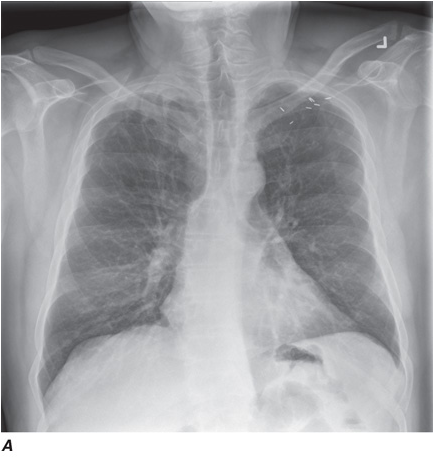

Computed tomography (CT) offers several advantages over routine chest radiography (Figs. C-1A, B and C-2A, B). First, the use of cross-sectional images allows distinction between densities that would be superimposed on plain radiographs. Second, CT is far better than routine radiographic studies at characterizing tissue density, distinguishing subtle density differences between adjacent structures, and providing accurate size assessment of lesions.

CT is particularly valuable in assessing hilar and mediastinal disease (which is often poorly characterized by plain radiography), in identifying and characterizing disease adjacent to the chest wall or spine (including pleural disease), and in identifying areas of fat density or calcification in pulmonary nodules (Figs. C-2A, B). Its utility in the assessment of mediastinal disease has made CT an important tool in the staging of lung cancer, as an assessment of tumor involvement of mediastinal lymph nodes is critical to proper staging. With the additional use of contrast material, CT also makes it possible to distinguish vascular from nonvascular structures, which is particularly important in distinguishing lymph nodes and masses from vascular structures primarily in the mediastinum, and vascular disorders such as pulmonary embolism.